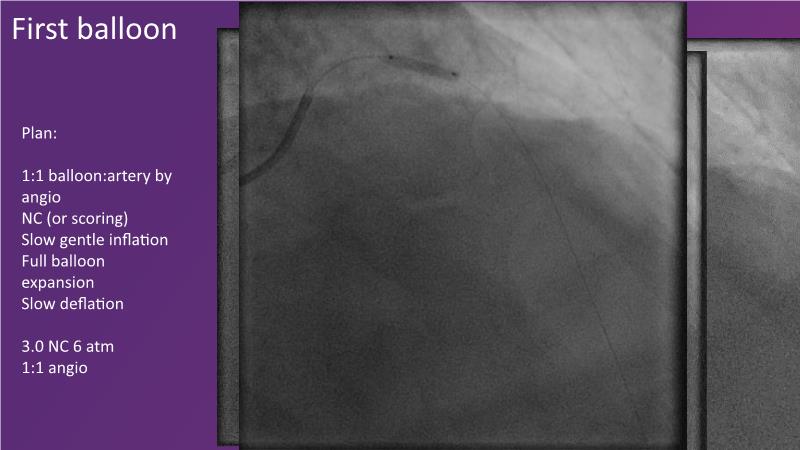

- To discuss how sustained limus release technology can broaden DEB indications and reduce metal

- To learn about the importance of vessel preparation and which tool to use when

- To review clinical scenarios when a stent is not required